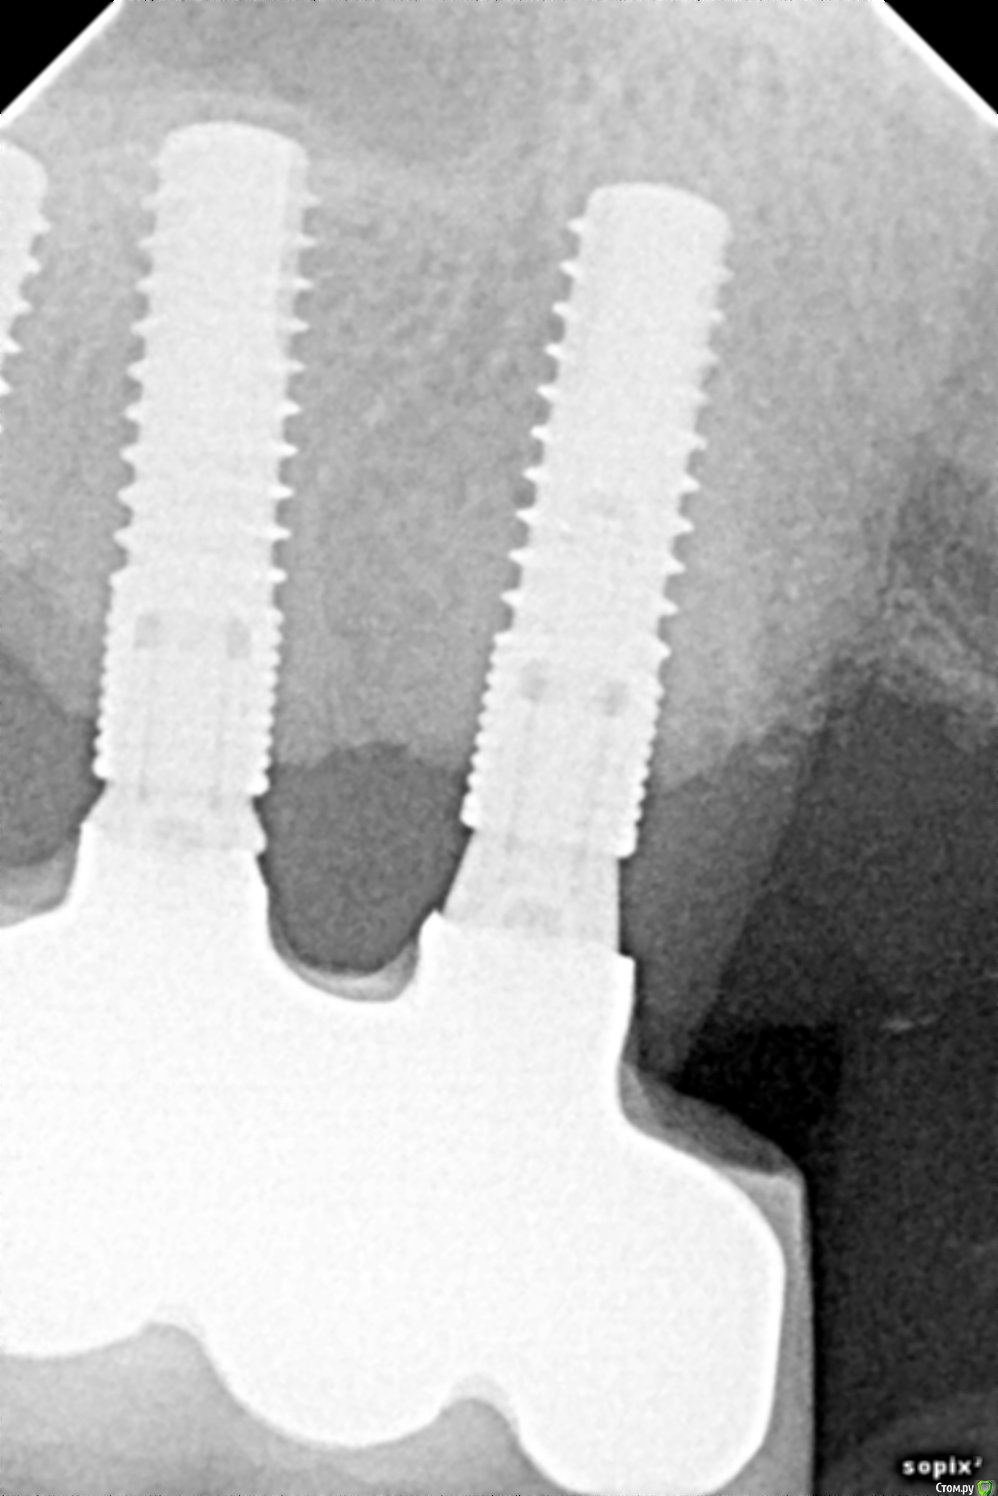

Имплантаты Конмет, установлены и запротезированы в 2010-2011 г. На данный момент пациента беспокоит только наличие сколов керамики. Учитывая атрофию костной ткани ( особенно у 1.7), какую хир. подготовку можно провести? Стоит ли объединять данные имплантаты с другими ( установленными в 2017 г. во фронтальном отделе)? И самое главное: какие возможны последствия (появление воспаления или подвижности), через какое время и как они могут сказаться?

post-46579-0-84594000-1499673812_thumb.jpg